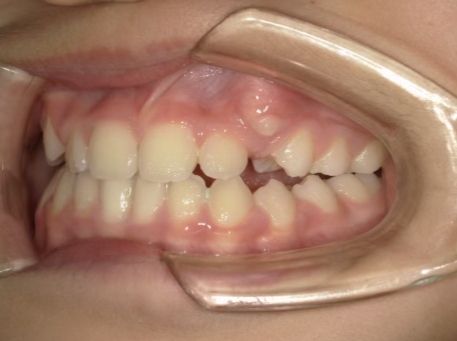

治療中④ 小4:10y1m

左上3が八重歯で萌出中